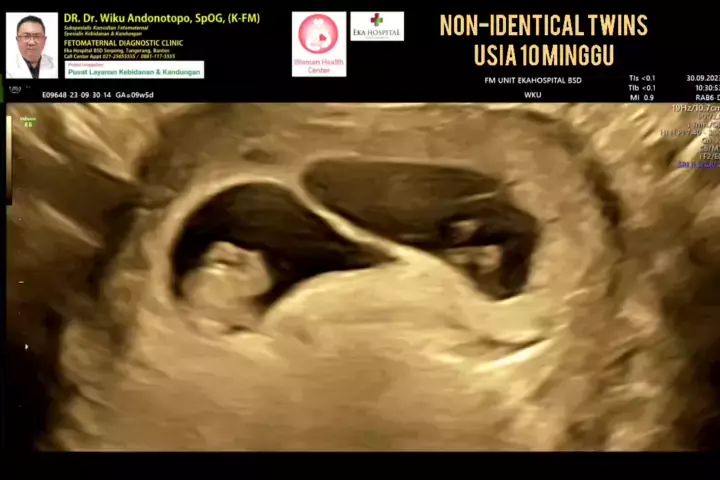

Kehamilan kembar non identik 10 weeks..... #drwikuandonotopo #drwiku_andonotopo #polikandunganekahospitalbsd #fetomaternalekahospitalbsd #usgfetomaternalekahospitalbsd #konsultanfetomaternalekahospitalbsd #ekahospitalbsd #ekahospitalcibubur #ekahospitalbekasi #ekahospitalpekanbaru #fetomaternalbekasi #fetomaternalcibubur #fetomaternal #konsultanfetomaternal #usg #usg4d #perkembanganbayi #perkembanganjanin # #melahirkannyaman #melahirkannormal #melahirkancesar #janin #lahiran #melahirkan #mel...